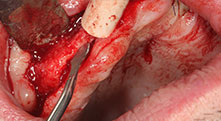

Бихте ли описали накратко, например, Вашия метод за мобилизиране на костни блокове за трансплантация?

Брату: Ние предпочитаме да събираме кост от външната страна на гребена в задната част на долната челюст. След разрязване на меките тъкани, ние използваме новите триони, за да определим количеството кост, което ще събираме. С този подход, ние използваме трионите за цялата препарация в почти 80% от случаите. Може да използваме и други пиезо инструменти и накрая длето за мобилизиране на блока. Ние смятаме, че това е изключително ефективна хирургична техника.

Брату: Ние предпочитаме да използваме техниката "сандвич" за аугментация в страничната долна челюст. Покритие на костта се подготвя с пиезо трион и кресталният фрагмент се фиксира с микровинтове. Поставяме смес от автогенна костна присадка и ксеногенен костозаместител между тях. Това работи много надеждно. Трябва винаги да осигурявате достатъчно оразмерени вертикални срезове при шиниране на алвеоларния гребен в долната челюст. В противен случай, костта лесно може да бъде счупена.